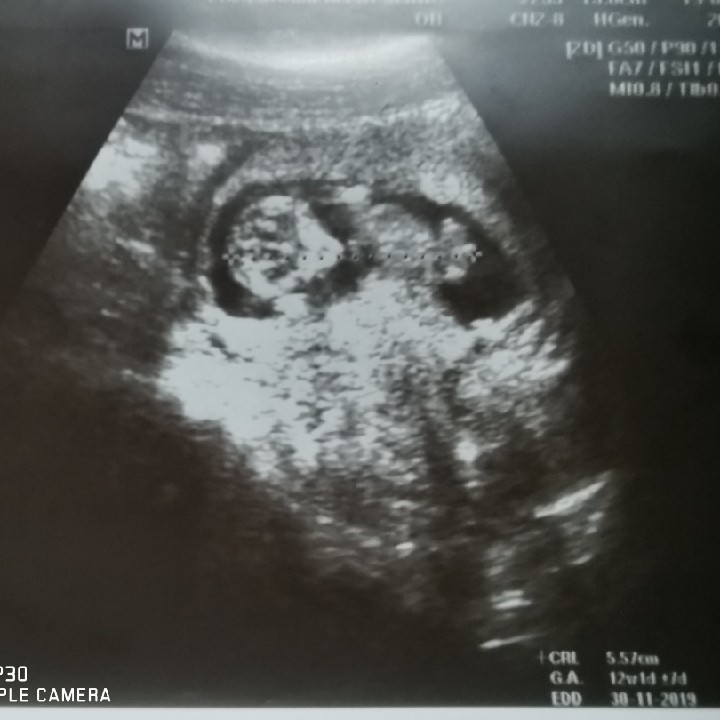

13w 4d ตอนนี้เตะเก่งมากๆ ครับ #ทีมธันวา

12 week ค่ะ เพิ่งซาวน์เมื่อวานนี่เอง 😊